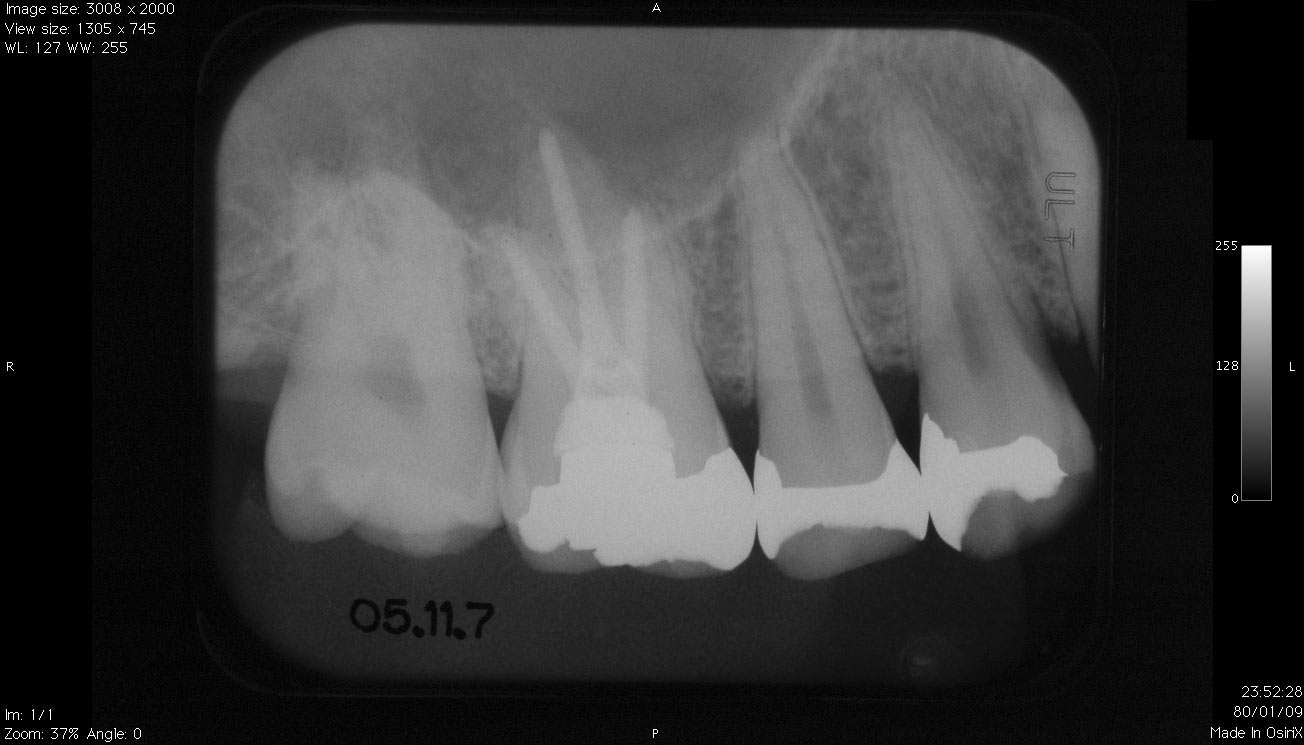

デンタルX線写真

• 5番が歯根破折を起こしていますが。歯根周囲病巣が上顎洞に波及(交通)している?。